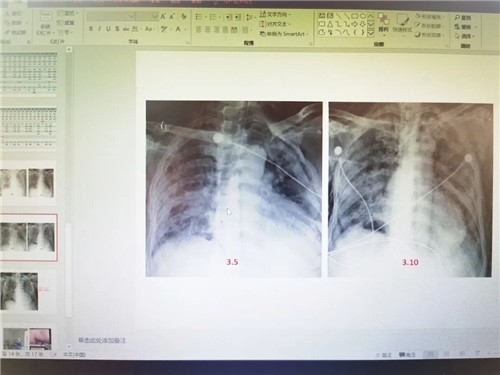

“我们此时开展会诊,不是为了解决疑难病症,而是希望通过流程的规范,最大限度降低重症患者病亡率。”康焰说,重症患者的救治结果与救治规范与流程关系密切,需要依据患者的状况及时优化与调整,而新冠肺炎重症患者,往往伴随有基础疾病,且合并症严重,救治过程中除了密切的器官功能监测与精准、恰当的器官功能支持措施外,原发病与合并症的治疗非常重要,这就需要重症医师与多个专业的医生一起讨论,从不同角度来优化治疗方案,这对最终改善重症病人的治疗结局有决定性的作用。

据了解,经过四川援湖北医疗队前方工作组拉网式排查以及重症救治MDT讨论组的初步筛查,目前医疗队的重症病例位46例。医疗队计划在3月20日前完成对管理范围内所有重症病人的MDT会诊工作。